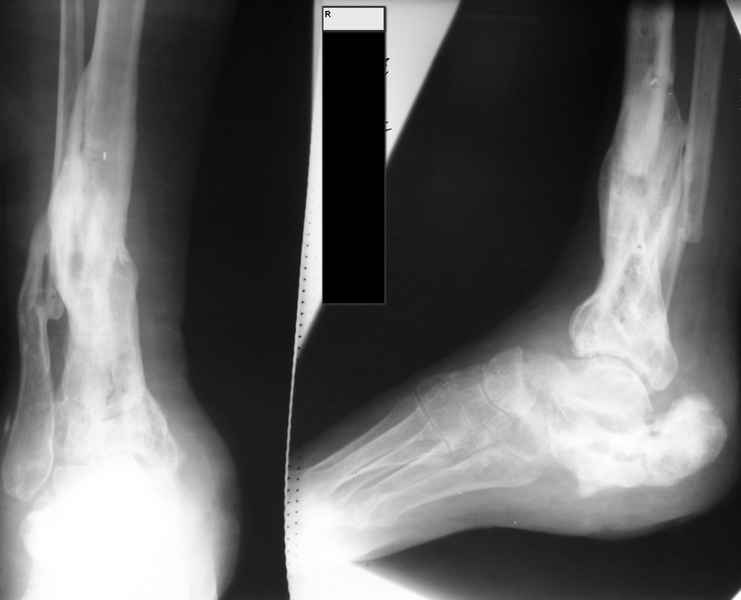

Молодая девушка со сросшимися многооскольчатыми переломами пяток и голеней.

Young girl with fractures of the calcaneus

Больная Н., 25 лет, падение с высоты (2008 г.). Жалобы на боли в области голеностопных суставах, в области пяток при ходьбе. Лечилась в аппаратах внешней фиксации по поводу открытых оскольчатых переломов обеих голеней, переломов пяток. Далее по поводу несросшихся переломов голеней –ЧКОС аппаратами внешней фиксации. Переломы срослись, аппараты демонтированы весной 2010г. В левой пяточной области в месте проведения спицы имеется сукровичное отделяемое. При ревизии гноя нет. Чем помочь девушке?

Patient N., age 25, falls from heights (2008). Complaints of pain in the ankles, in the heel when walking. She was treated by external fixation on open comminuted fractures of both legs, fractures of the calcaneus. Then she was treated by external fixation from nonunion of both legs. Now fractures are fused, apparatuses removed in the spring of 2010. How to help a girl?